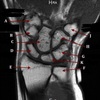

8

Q

What is letter B?

A

HEAD OF HUMERUS

How well did you know this?

1

Not at all

2

3

4

5

Perfectly

9

What is letter C?